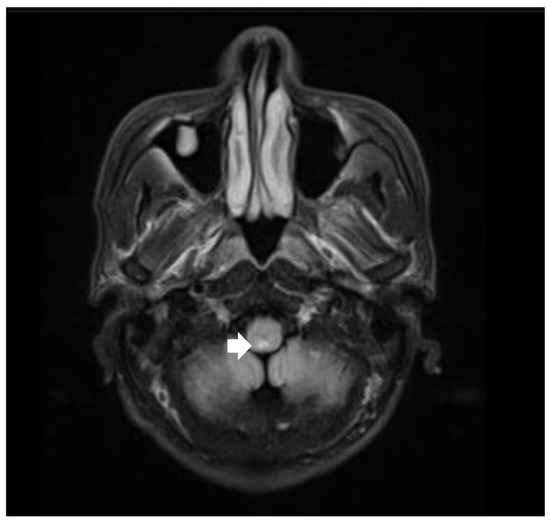

Brain MRI showed new lesions in the dorsal part of the medulla oblongata, pons, and mesencephalon (Figure 3). A serum anti-aquaporin 4 antibody test was positive. Based on typical brainstem syndrome manifestations, the presence of periependymal brain stem lesions in MRI, and the positive AQP4 antibody test, this patient was definitively diagnosed with NMOSD. After readmission, the patient was referred to the ICU due to aspiration pneumonia caused by dysphagia, as well as the recurring hiccups and vomiting. After strong anti-infection therapy, the patient’s body temperature returned to normal, and chest CT showed inflammation resorption and improvements in inflammatory factors. Nevertheless, he had a respiratory arrest followed by a subsequent cardiac arrest. He was successfully resuscitated with epinephrine injection and cardiopulmonary resuscitation. Considering the patient’s pulmonary infection was under control, and his symptoms were not consistent with the presentation of septic shock, we attributed the cause of the slow heart rate and low blood pressure to his NMOSD. The patient was treated with one course of intravenous methylprednisolone, one course of therapeutic plasma exchange, and one course of IVIG before his blood pressure and heart rate were stable within the normal range. He was then transferred to another hospital for rehabilitation. After discharge, the patient chose oral steroids and azathioprine as a disease-modifying therapy.

Figure 3.

Brain MRI revealed bilateral high-intensity lesions in the dorsal part of the medulla oblongata, periependymal surfaces of the pons and dorsal midbrain on axial fluid attenuated inversion recovery (FLAIR) sequence.